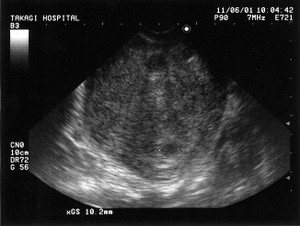

突然ですが、今年の1月初め、我が家の愛犬がお亡くなりになりました。享年2.5歳。ペギニーズとシーズーのMIX。昨年末に歯石を取りに獣医さんに行ったら、麻酔の関係で血液検査。結果は生きているのが不思議なくらいの数値。腎臓の機能がほとんど無い状態。歯石どころではなく、即、治療開始。